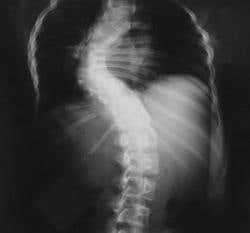

Scoliosis affects as many as 1 in 50 adult women and 1 in 200 men, causing their spines to curve from side to side into unnatural “C” or “S” shapes. In severe cases, it is treated by grafting sections of bone or metallic fixators onto the spine to help straighten it. But this “spinal fusion” surgery usually cannot…